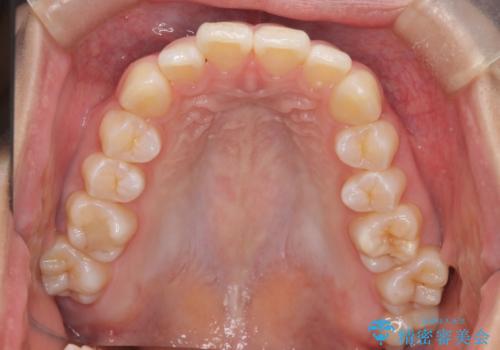

- 出っ歯を治したいとのことで来院されました。

目立たない装置が希望とのことでハーフリンガルで治療をすることとしました。

当院では裏側矯正という方法も提供しています。裏側矯正は、装置を歯の裏側に取り付けるため、外側からは目立ちにくくなります。この治療法は、見た目に気を使いたい方に特におすすめです。